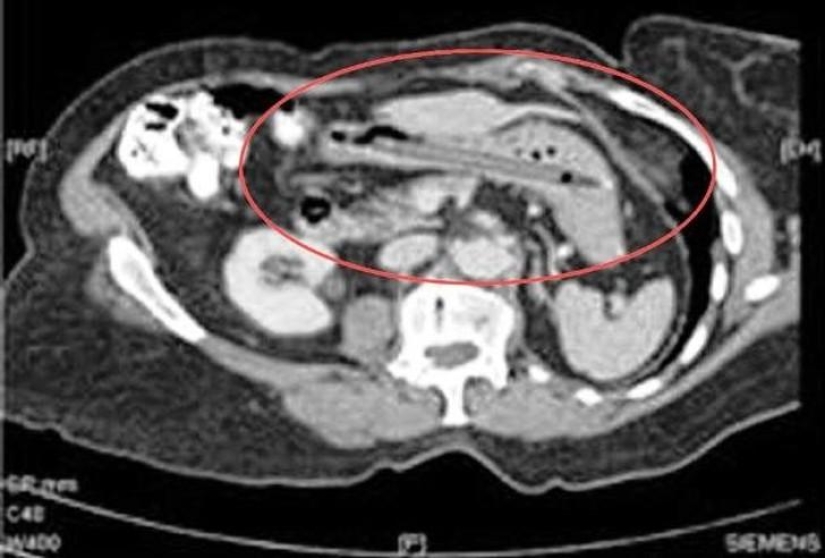

Botella.